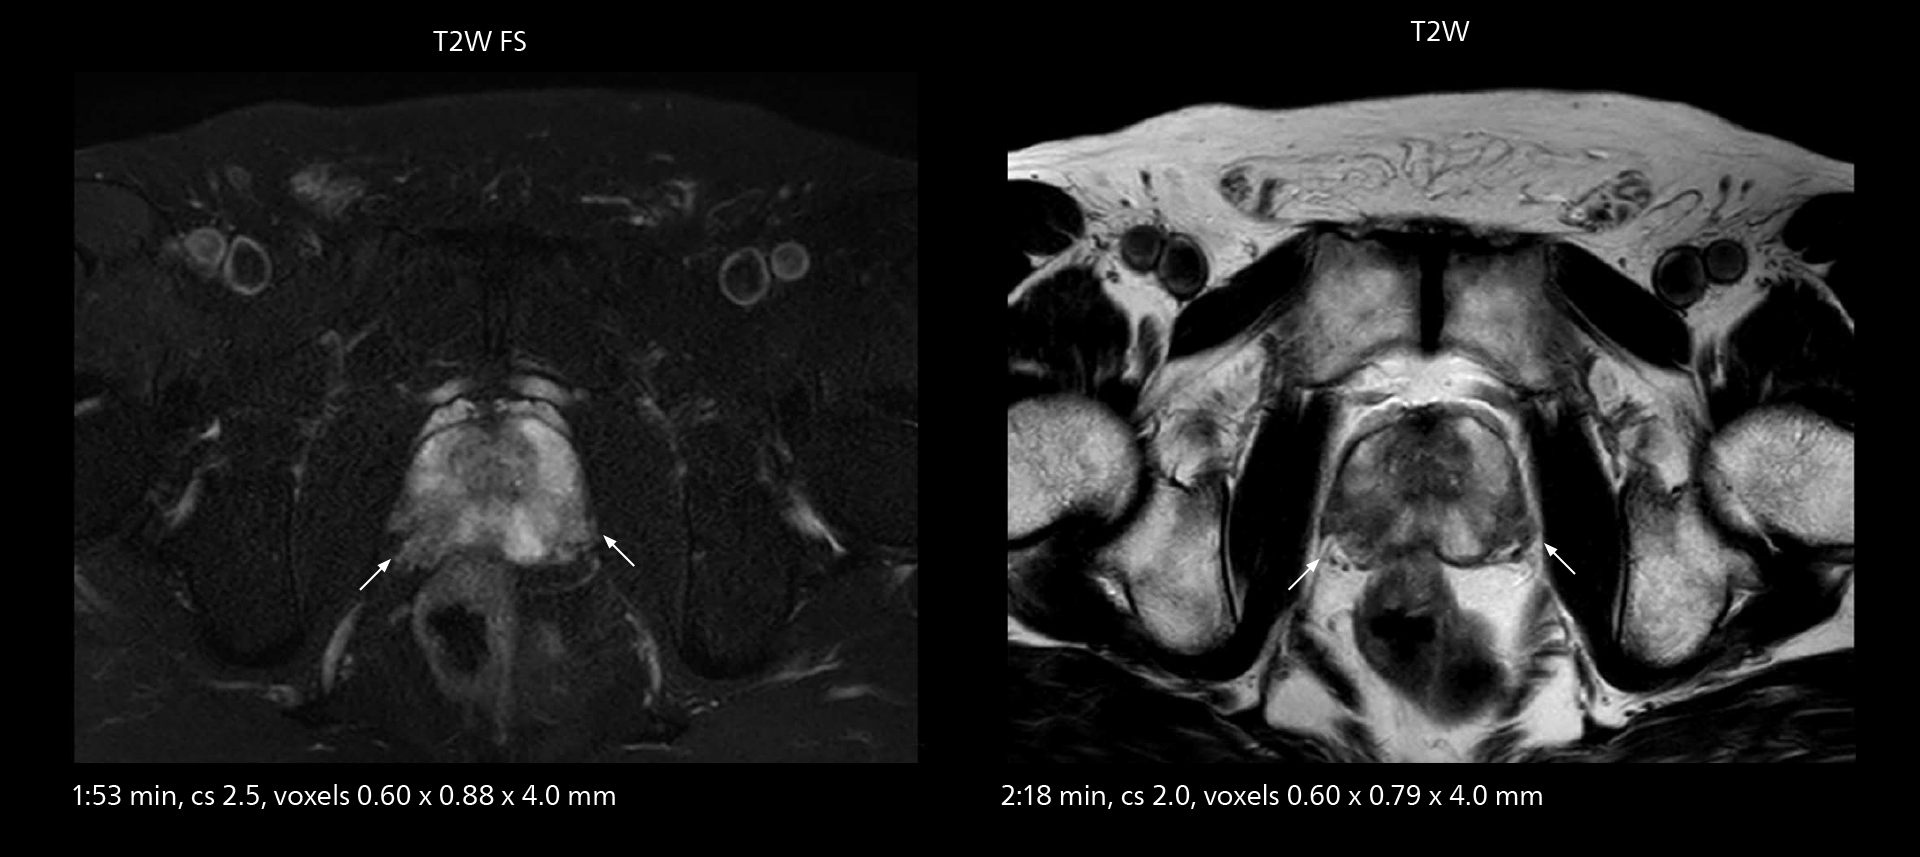

The high performance of the Vega HP gradients is particularly impressive in DWI. “The Vega HP gradients enable us to scan faster and use b-values as high as 2000, for example in prostate DWI and in DWIBS, which provides image quality that is remarkably improved over the previous system and we are able to more easily see lesions.”

MRI of prostate

Examples of prostate imaging showing faster scan times and improved resolution illustrate the power of SmartPath to Elition X in this case of prostate cancer with PI-RADS score 4.